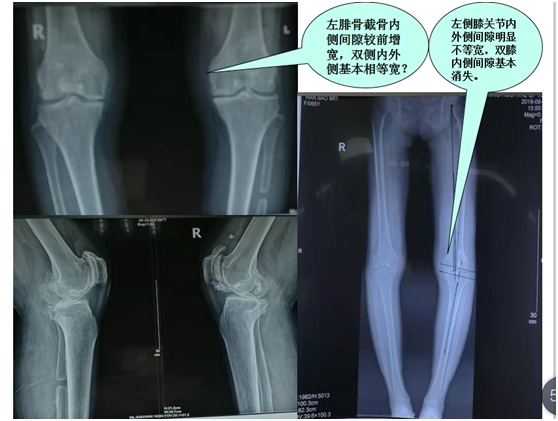

经科室讨论后:在局部麻醉行双膝关节腔靶向介入臭氧治疗+激光清理术;3天后又在硬膜外麻醉下左腓骨上段截骨(减压)均衡术+关节腔靶向介入臭氧治疗+激光清理术;6天后又在局麻下双膝关节腔靶向介入臭氧治疗+激光清理术;14天后又在局麻下双膝关节腔靶向介入臭氧治疗+激光清理术,术后患者双膝关节疼痛逐渐消失,左膝关节内翻畸形步态明显改善(见图片三  DR片 显示膝关节内侧间隙增宽);随访至今膝关节疼痛没有复发,定期3月次门诊复查保养康复,生活自理,能够超市买菜,做日常家务照顾里外孙上学。

图片三: DR 片膝关节退行性变内翻畸形,截骨前后关节间隙宽窄对比